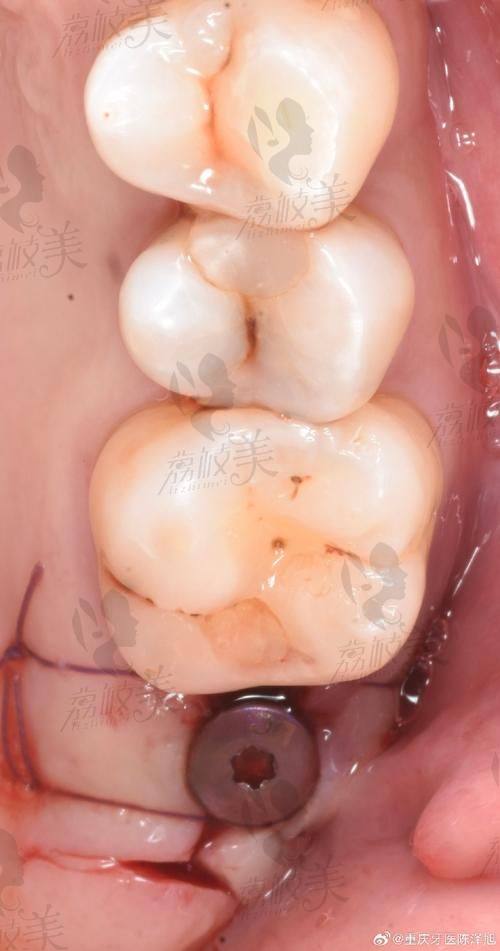

数字化导板和CT三维成像系统配合精细评估,有效避免神经损伤、位置偏移等问题;让植体稳固扎根,并实现自然、美观的牙冠修复。

3. 数字化微创植入:在数字导板辅助下,严谨打孔并植入种植体。过程约30分钟。

4. 术后复诊与修复:术后会定期检查种植部位愈合情况,并在术后3~6月安装牙冠。